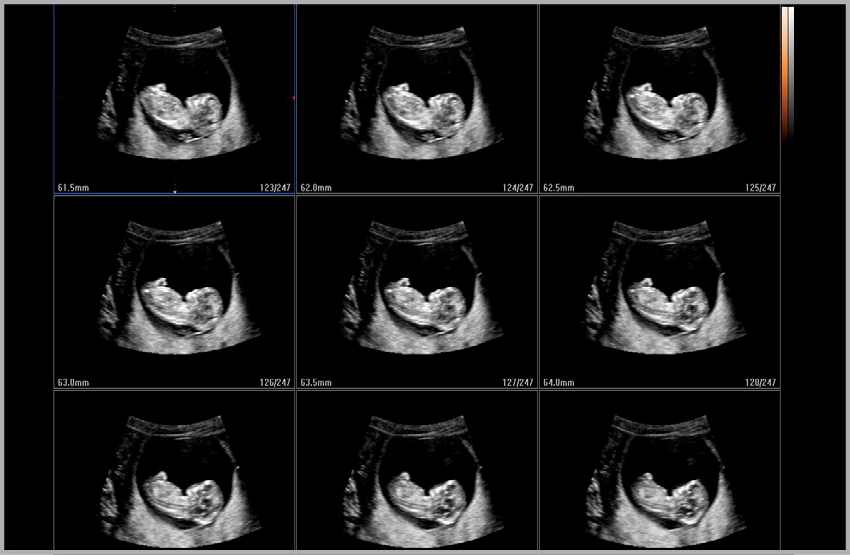

Модуль 5D Heart Color - позволяет исследовать структуры сердца плода на предмет потенциальных нарушений кровотока, что является важной составляющей эхокардиографического исследования плода. Используя объемные данные STIC и ЦДК, строятся 9 стандартных эхокардиографических срезов плода на одном экране.

Модуль 5D NT - программа автоматического измерения ТВП и интракраниального пространства плода в режиме объемного сканирования.

Модуль 5D Follicle - программа автоматического определения и измерения размера и объема фолликулов в режиме объемного сканирования.

Модуль STIC - объемная динамическая визуализация сердца плода.

Модуль HDVI (High Definition Volume Imaging) - повышение четкости изображения границ тканей с разной эхо-плотностью в объемном изображении (диагностика тонких повреждений тканей, дефектов мозга плода, стенок и клапанов сердца плода).

Объемный датчик 1-8 МГц (монокристальный) – Трехмерные абдоминальные исследования, акушерство (трехмерное УЗИ плода) и гинекология.

1-й треместр

Пуповина в PW

Сердце плода

Пупочная артерия

Раннее исследование плода при MSV